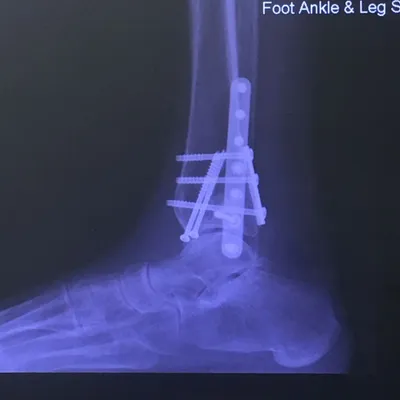

Preop and Postop ORIF Posterior Malleolus Fracture with associated Fibular fracture

Preop and Postop Trimalleolar Fracture with Fixation of Posterior Malleolus Fracture

Postop

Both the lateral and medial malleolus with fractures with the lateral malleolar fracture classified as a Weber B (at the level of the ankle joint) and the medial malleolar fracture almost transverse (Left x-ray). This is indicative of a Supination External Rotation (SER IV) injury. The fractures are repaired using open reduction with internal fixation (ORIF) technique and fixated with screws and a surgical fractue plate located at the fibular (Right x-ray).

Below is the same patient seen above after surgical repair with open reduction and internal fixation with screws for the medial malleolar fracture and screws and plates for the lateral mallolar fracture. Note the even joint spacing across the ankle mortise after correction (left) that is not evenly spaced in the pre-surgical picture (above right).